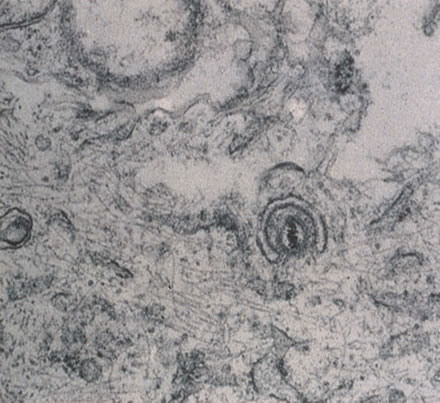

The herpes simplex virus (HSV) is a common cause of ocular, perioral, and genital infection in humans. The viral particle consists of a core of double-stranded DNA surrounded by a protein capsid and lipid envelope. After the primary infection, HSV survives in latent form inside sensory nerve ganglia and may reactivate at any time producing recurrent disease. HSV type 1 accounts for the majority of herpes labialis and ocular herpetic infections. HSV type 2 causes genital herpes infections.1

Any cell type may be infected, appearing larger than normal (cytomegalic) and demonstrating eosinophilic intranuclear “owl's eye” and smaller intracytoplasmic viral inclusion bodies, which are better seen with Giemsa or Papanicolaou's stains (Fig. 8). Histologic examination of tissue specimens, including bronchoalveolar lavage fluid and urine, may be useful for diagnosis.